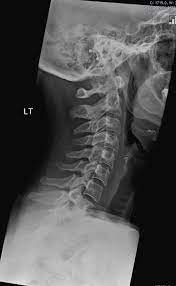

This procedure may be used to diagnose back or neck pain, fractures or broken bones, arthritis, degeneration of the disks, tumors, or other problems. Enter search terms and tap the search button. They show pictures of your internal tissues, bones, and organs. Please understand that our phone lines must be clear for urg. Here's what to expect with this painless procedure and why your dentist may recommend it.

This procedure may be used to diagnose back or neck pain, fractures or broken bones, arthritis, degeneration of the disks, tumors, or other problems. It's commonly done after someone has been in an automobile or other accident. They show pictures of your internal tissues, bones, and organs. Here's what to expect with this painless procedure and why your dentist may recommend it. Please understand that our phone lines must be clear for urg. Enter search terms and tap the search button.